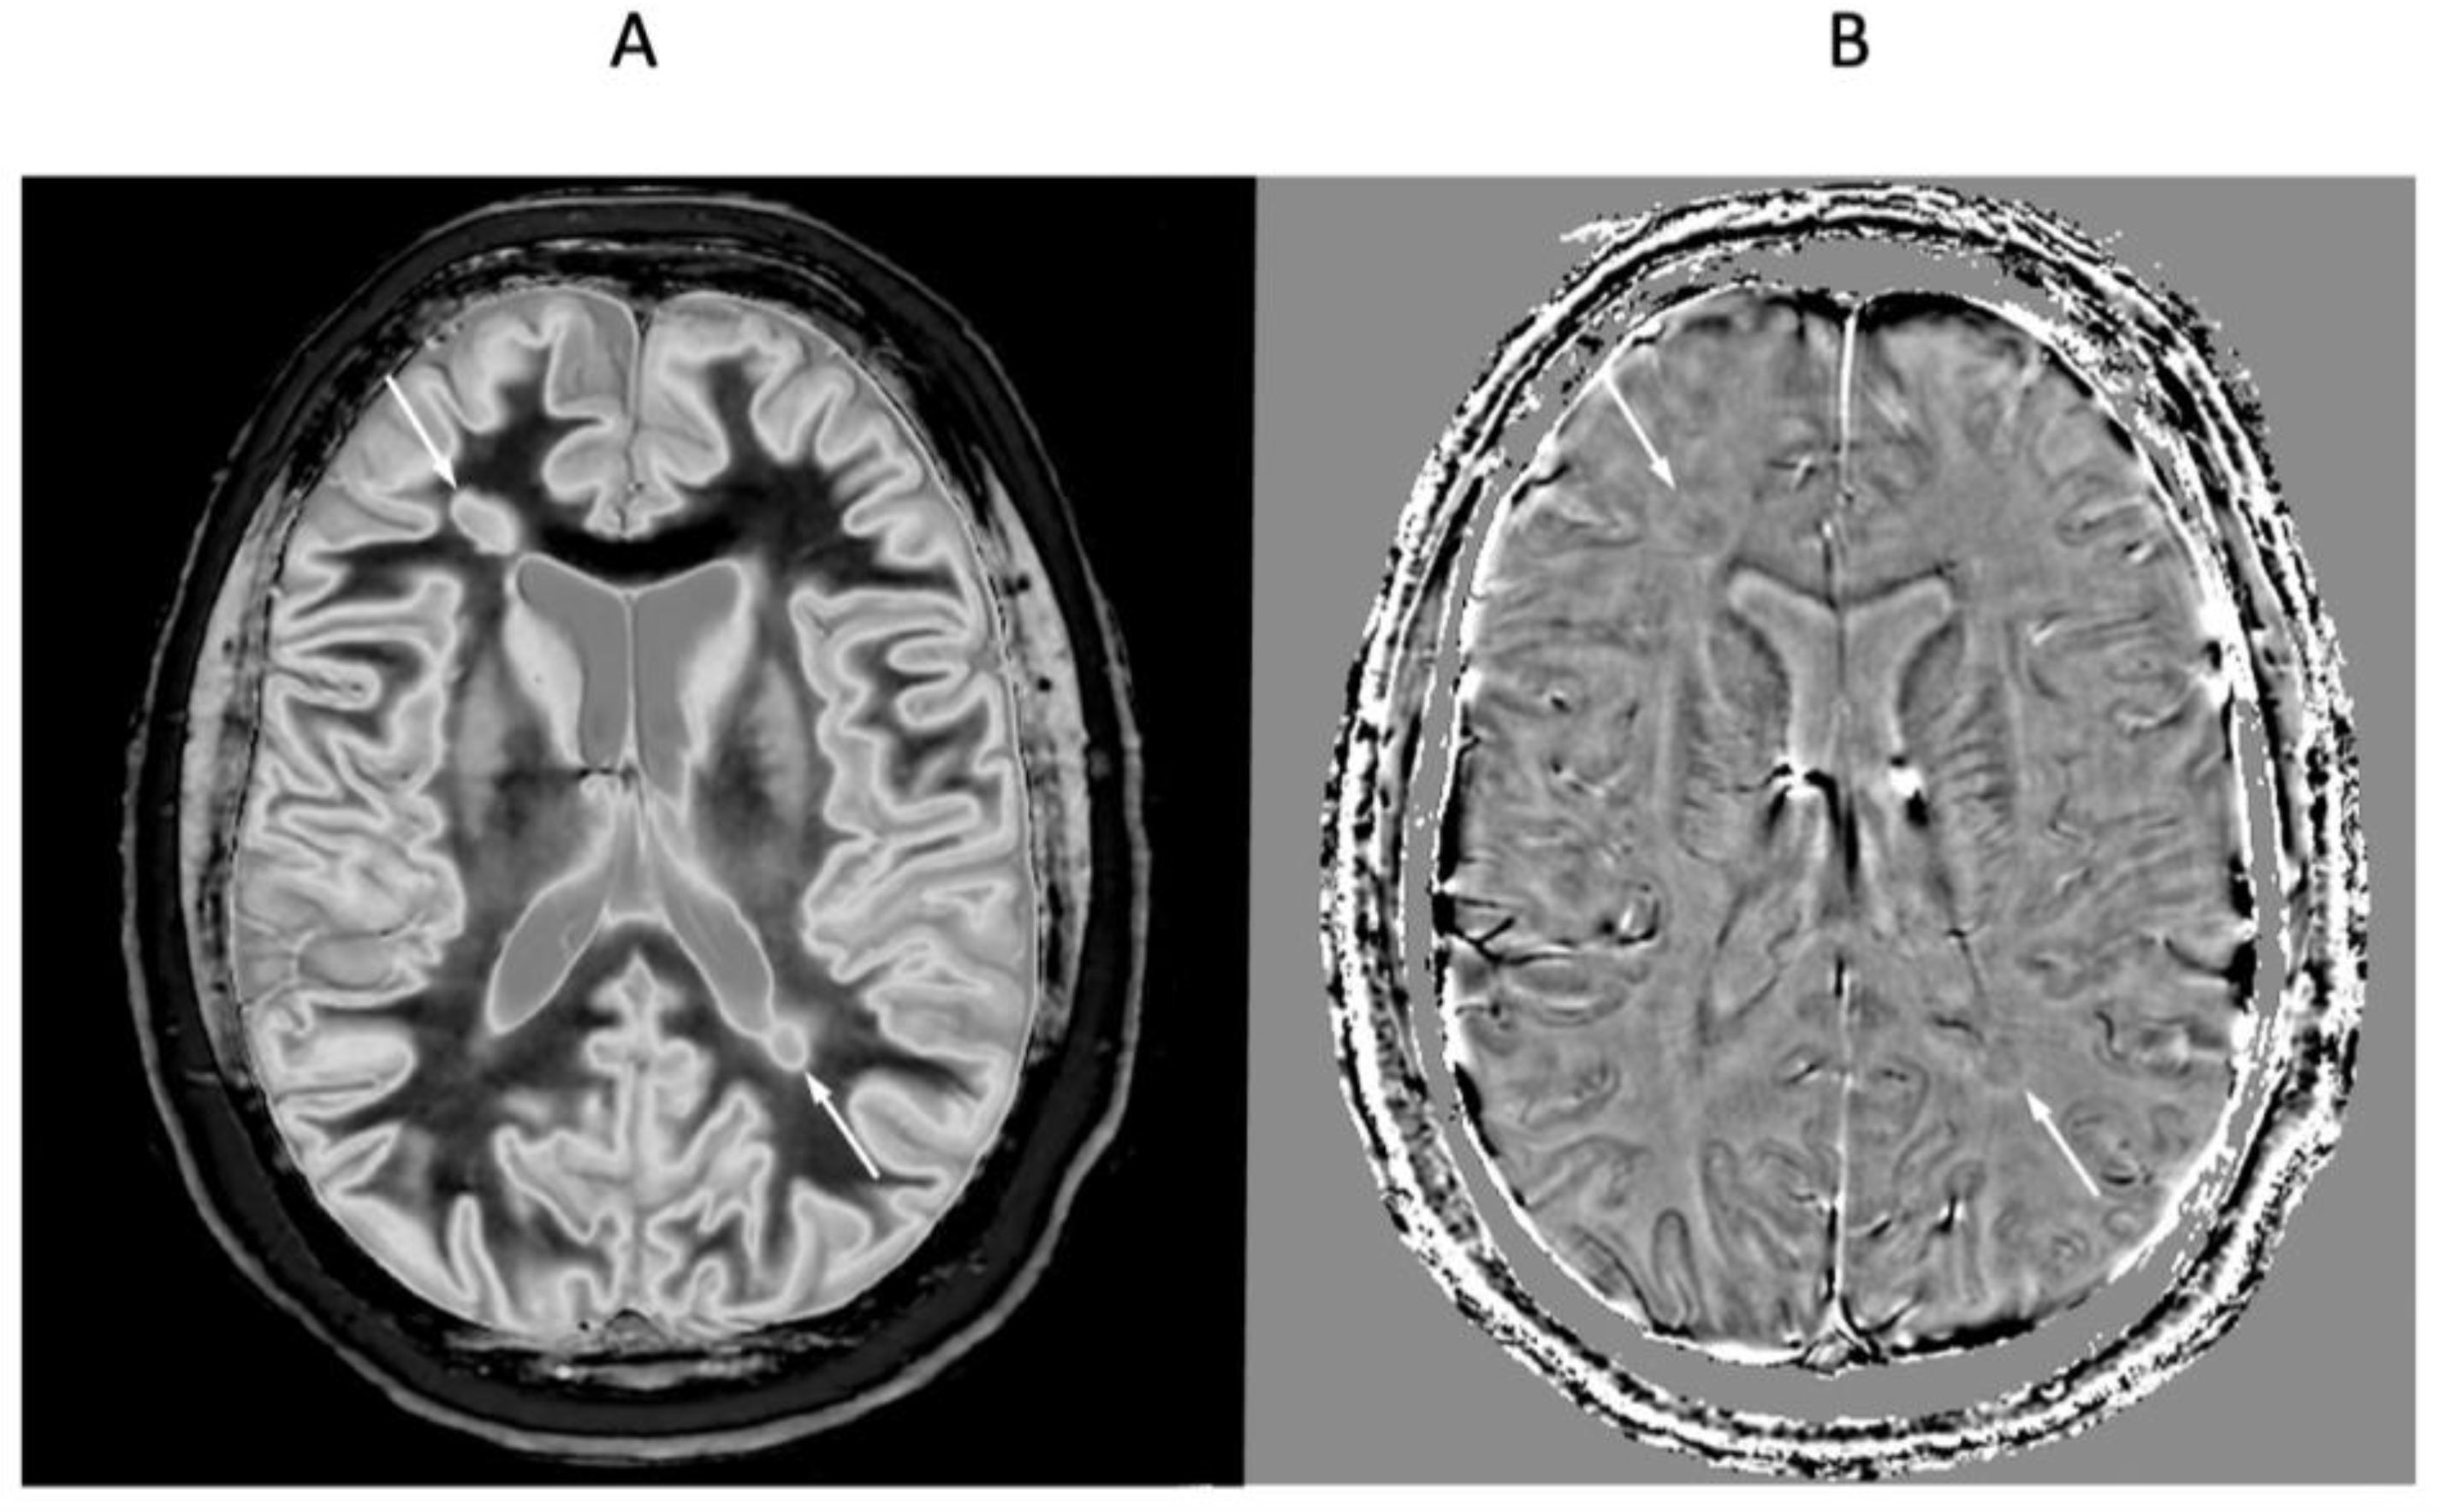

Figure 12 shows a 41-year-old female patient with MS during a relapse. Wide mD dSIR (Figure 12A) and phase filtered susceptibility weighted gradient echo (Figure 12B) images are shown. The dSIR image shows well defined high signal boundaries around two lesions (Figure 12A, white arrows). These lesions show less obvious paramagnetic rim signs on the filtered susceptibility weighted images (Figure 12B, white arrows). The high signal in Figure 11A could be due to increased T1 in the lesions beyond the second T1 nulling value and/or reduction in T1 in long T1 lesions due to free iron.

Figure 12.

Forty-one-year-old female patient with MS during a relapse. Wide mD dSIR (A) and phase filtered susceptibility weighted gradient echo (B) images. The dSIR images show well defined high signal boundaries around two lesions in (A) (white arrows). These lesions show less obvious rim signs on the susceptibility weighted images (B) (white arrows).